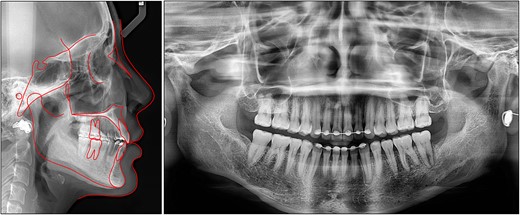

After treatment, class I canine and molar relationships were obtained on both sides with a normal overjet and positive overbite (Fig. 5). The posttreatment lateral cephalometric evaluation showed an improvement in both anteroposterior (point A-nasion-point B angle, 3.1°) and vertical dimensions (Frankfort mandibular angle, 31.0°). The posttreatment panoramic radiograph showed adequate root parallelism without any sign of root resorption (Fig. 6). The lateral cephalometric superimpositions confirmed the intrusion of the maxillary molars, the extrusions of the incisors, and the counter-clockwise autorotation of the mandible (Fig. 7).

Overall and regional cephalometric superimpositions: black, pretreatment; red, posttreatment.